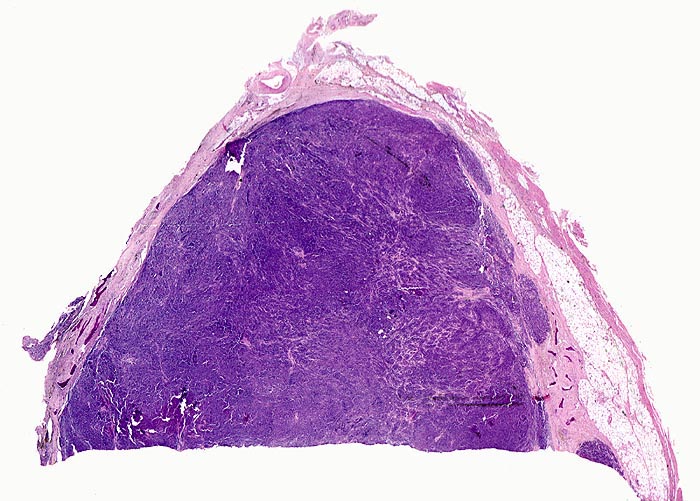

Makroskopisch sind die runden Osteolyseherde gefüllt mit einer weichen gelatinösen fischfleischartigen grauroten Tumormasse. Gelegentlich findet sich anstelle von Osteolysen eine diffuse Osteoporose. In der Knochenmarkbiopsie sind die Plasmazellen vermehrt. Im Gegensatz zu den kleinen Aggregaten von 5 bis 6 Plasmazellen rund um Markarteriolen bei reaktiver Plasmozytose bilden Plasmazellmyelome grössere Herde, Knoten oder flächenhafte Infiltrate. Für ein Plasmazellmyelom spricht eine tumorale Masse von Plasmazellen, welche das ortsständige Knochenmark verdrängt. Wenn über 10% des Markvolumens von klonalen Plasmazellen eingenommen wird, ist die Diagnose eines Plasmazellmyeloms sicher. Je nach klinischer Präsentation liegt dann eine symptomatische oder asymptomatische Verlaufsform vor. Die neoplastischen Zellen produzieren meist monotypische zytoplasmatische Ig (meist IgG, gelegentlich IgA, selten IgD, IgE oder IgM). 85% produzieren Schwerketten und Leichtketten, die restlichen 15% ausschliesslich kappa oder lambda Leichtketten (> 1097). Die klonalen Paraproteine können in den meisten Fällen mit einer Serumelektrophorese oder Urinelektrophorese gemessen werden können.

• Knochenmarkstanze mit nodulärer Hyperzellularität des blutbildenden Marks.

• Keine wesentliche Osteopenie.

• In den hyperzellulären Arealen dichte Rasen neoplastischer atypischer Plasmazellen.

• Ausserhalb der Plasmazellrasen findet sich spärlich residuelles blutbildendes Knochenmark.